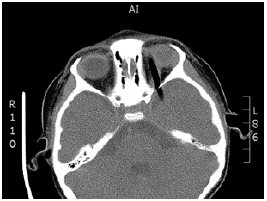

The tomography showed an intraorbital route of the foreign body towards the right side, and above the left eyeball towards the temporal lobe; no intraconal or intraocular lesions were evident, and no intracranial, subdural or epidural hematomas or retroconal bleeding were observed (Figures 1 and 2).

After the removal, a control CT of the skull and orbits was performed, reporting left eyelid hematoma and in the left upper rectus and lateral rectus muscles. A frontal subdural and temporal left laminar hematoma was observed in the cranial cavity, without compressive effects.

In the CCU, the child received antibiotic synergy with vancomycin 220mg every 6 hours intravenously, later increased to 250mg every 6 hours, and ceftriaxone 1g every 12 hours intravenously; anti-inflammatory management with intravenous dexamethasone and mechanical ventilation was indicated. The control CT scan of the orbit taken the first post-operative day showed a decrease in the upper subperiosteal hematoma and hematoma adjacent to the lateral rectus muscle; this retroconal hematoma had orbital extension and persisted on site in the three thirds of the orbit, greater in the anterior third and without signs of optic nerve compression or other alterations of intraorbital structures. In addition, control CT scan of the skull showed subarachnoid hemorrhage over the tentorium of the left cerebellum and falx cerebri, as well as acute frontal basal left and temporal left subdural hemorrhage with an extension of 5mm.

Taking into account the satisfactory evolution the following day, the patient was sent to the pediatric floor, where she evolved satisfactorily without neurological or visual impairment, nor need for new surgical interventions. The last control CT scan of the orbit revealed slight reduction of retroconal hematoma, persistence of left frontal and temporal subdural collection and slight subfalcine hernia of 3mm, without evidence of transtentorial hernia, expansive lesions, cysts or calcifications.